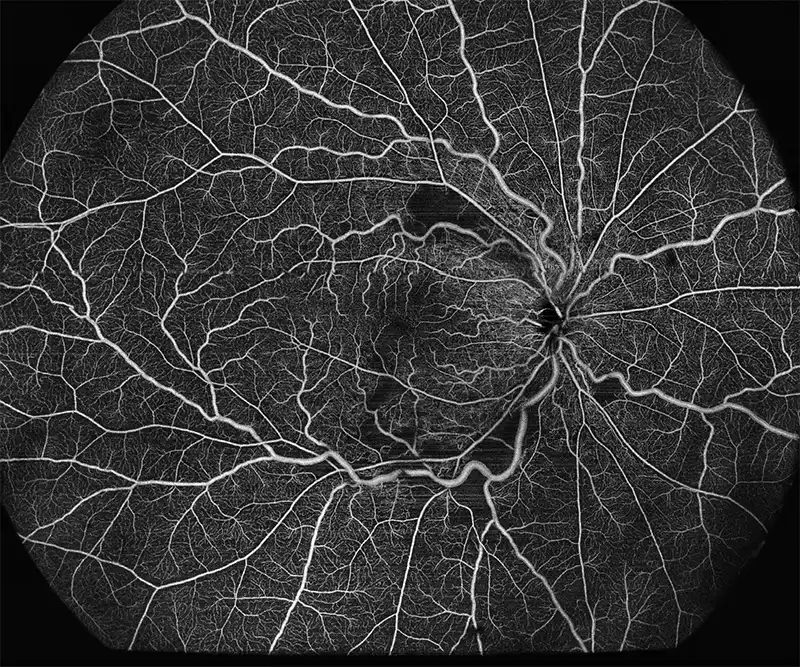

BMizar (BM-400K) es el OCT más potente de la industria con una fuente de barrido de 400 kHz. Su excepcional diseño óptico eleva la experiencia de la Angiografía OCT a un nivel sin precedentes. Con imágenes de alta definición de la retina, la coroides y el segmento anterior, cubre sin esfuerzo un área increíblemente grande en un solo escaneo (logrando un OCTA de 24 mm de ancho en solo 7-15 segundos).

Esta tecnología revolucionaria es un cambio de juego para las prácticas clínicas, particularmente en el diagnóstico y tratamiento de enfermedades como DR, RVO, RAO y más. Además, el BMizar ofrece un amplio rango de adaptación dióptrica, lo que hace factible realizar todo tipo de escaneos OCT/OCTA en pequeños animales como conejos, cobayas e incluso ratones sin necesidad de lentes adicionales. Es verdaderamente un equipo de ensueño para cualquier usuario de OCT.

Galería OCTs del TowardPi BMizar